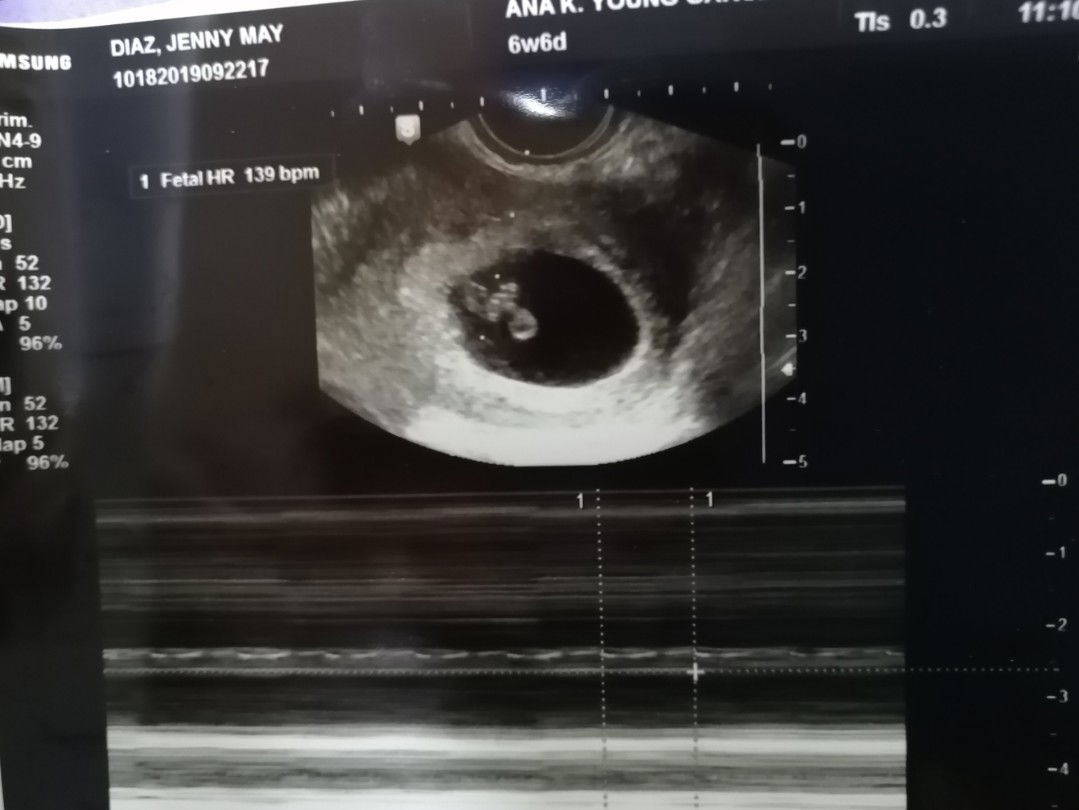

Anembryonic Pregnancy

1st pregnancy anembryonic pregnancy 2nd pregnancy now... 8 weeks na. Pero walang signs of cravings and nausea. Sana normal please Lord. Thanks be to God!

Ok lang yan Importante meron na sya heartbeat Ang nakaatakot kasi no sign of concepcion un pala wala heartbeat..